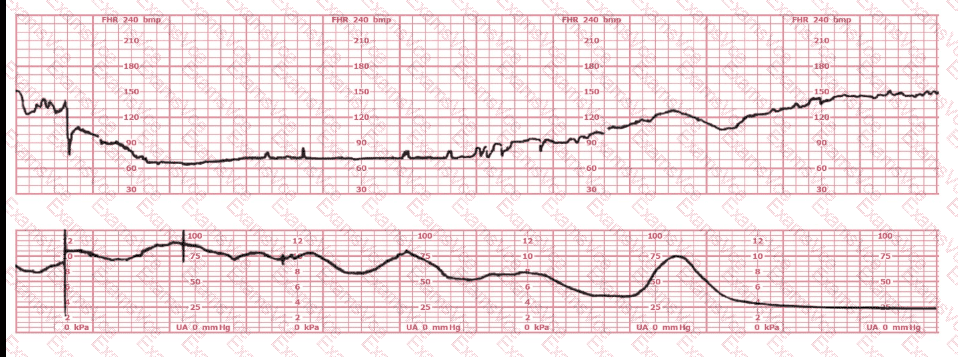

In this tracing, the fetus demonstrates:

– A prolonged deceleration with subsequent recovery,

– Presence of baseline variability,

– Return toward baseline but not immediately normal.

AWHONN and Simpson state that any prolonged deceleration automatically places the tracing in Category II unless variability is absent (which would escalate it to Category III). Because variability is present, it cannot be Category III.

Therefore, by NCC standards, this tracing is Category II.